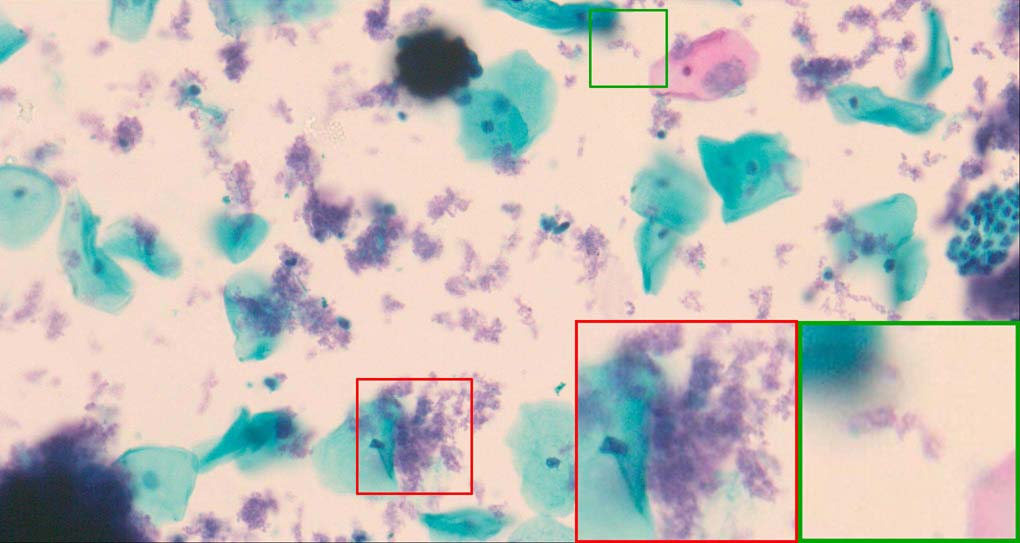

A good image fusion method should contain the following properties. First, it preserves both the details of small size objects and the integrity information of large size objects in the fused image, even in the case of the size of the interested objects varying largely in the image. For example, the cervical cell images from the microscope contain both small size isolated cells and large size agglomerates, which are both useful for cervical cytology [5]. Second, it should be efficient enough to handle large-scale data. For instance, it needs to process thousands of fields of view (FoV) in an acceptable time for the whole slide scanning in digital cytopathology [6], which requires to fuse a series of high resolution images captured at each FoV in a very efficient way. Third, it does not produce obvious artifacts. Despite being studied extensively, to our best knowledge, existing fusion methods may not meet these requirements simultaneously.

To demonstrate the effectiveness and efficiency of the proposed image fusion method , we conduct a set of comparative experiments on three image datasets. The first is composed by 8 pairs of multi-modal medical images and the second one contains 15 pairs of multi-focus gray or color natural images. These two datasets are often used in many related papers and some examples are shown in Figure 3(a) and Figure 3(b). The third one is a new multi-focus cervical cell image dataset collected by ourselves, which consists of 15 groups of color images and each group contains a series of multi-focus cervix cell images with size of or , etc. Some source examples are shown in Figure 3(c). Our source code implemented in C++ along with the new multi-focus cervical cell image dataset is available online.

Figure 9, Figure 10 and Figure 11 show the comparative fused results of the multi-focus cell images shown in Figure 3(c). For clarity, we also present a closeup view in the right-bottom of each sub-picture in Figure 9 and Figure 10. As shown in the close-up views of Figure 9, the fused images based on DSIFT, IM, MWGF and BF methods are extremely blurred in the boundary and fail to keep the details of cell nucleus. Furthermore, the DTCWT and NSCT based methods produce halo artifacts in the fused images, while GFF and CNN based methods fail to preserve the small cell nucleus. LP-SR based method nearly works fine which keeps the most of the details of the small size cells, but the integrity of the clustered large size cells is damaged. Fortunately, in our proposed method, the integrity of the clustered large size cells is preserved and most of the isolated small size cells are maintained from the original images, which demonstrates the best visual quality.

Similarly, as shown in the close-up views of Figure 10, the fused images from DSIFT, IM, MWGF and BF are blurred and lose some nucleus details, while the results from DTCWT, GFF, CNN and NSCT produce halo artifacts. LP-SR based method can keep details well but also produces halo artifacts and other noise. Our method can preserve the focused areas of different source images well without introducing any artifacts. For the example illustrated in Figure 11, the fused images generated by DSIFT, DTCWT, IM and NSCT all fail to preserve the focused areas of different source images and result in extremely blurred images. The GFF, CNN, MWGF and BF based method introduces a lot of color distortion of the nucleus regions and the obvious halo artifact. The result of LP-SR based method is close to the one of our method but introduces some odd color distortion. Again, our method produces fused image which can preserve the focused areas of different source images well without introducing any artifacts.